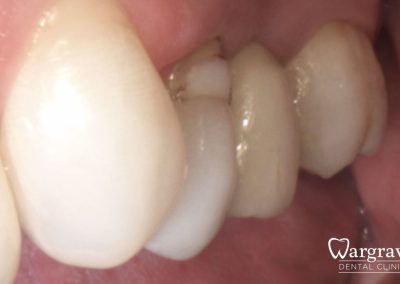

Healthy Smiles These are more advanced examples of different treatments available.All cases shown were carried out by Dr R Khurana unless otherwise stated. Immediate implants Anterior Mandible Bone Regeneration Anterior Mandibular Implant Bridge Maxillary Anterior Implant Bridge Implant stabilised ‘Life Like’ replacement dentures Implant Bridge after 10-years with zero bone loss Implant examples including ZBLC concepts Adhesive Bridge solution for a missing premolar Multidisciplinary care Orthodontics, Replacement veneers and composite bonding Adhesive Bridge solution for missing central incisors Replacement crown, Veneer and Composite Bonding Replacement Crowns and Veneer Injection Moulding using Composite Resin Equilibration Tooth Whitening to treat Developmental Discolouration